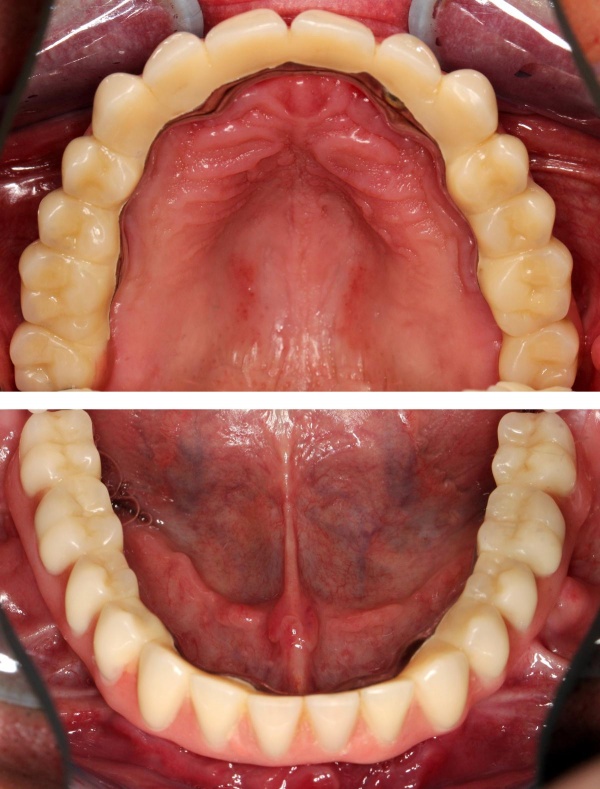

Im August 2012 erfolgten die 3D-gestützte Implantation (6 Implantate, Firma Nobel Biocare, System Active) im Oberkiefer mit Bone Split sowie eine An- und Auflagerungsosteoplastik vom linken Beckenkamm im Unterkiefer nach Entfernung der Miniimplantate (Abb. 3). Nach komplikationsloser Einheilung wurde im Dezember 2012 die Materialentfernung und Implantation im Unterkiefer (6 Implantate, Firma Nobel Biocare, System Active) durchgeführt (Abb. 4). Die Osseointegration verlief ungestört. Aufgrund der ungenügenden Weichgewebssituation im Unterkiefer erfolgte an jedem Implantat bei Freilegung eine Vestibulumplastik mit Einlagerung einer bioresorbierbaren Membran (Firma Botiss, Mucoderm, Abb. 5 und 6). Die endgültige prothetische Versorgung erfolgte durch den truppenzahnärztlichen Kollegen in der Stammeinheit des Patienten (Zahnarztgruppe Nordholz / SanZ Celle) mit einer gaumenfreien implantatgetragenen Teleskopprothese im Ober- und Unterkiefer, die eine festsitzend-herausnehmbare vollständige stomatognathe Rehabilitation des Patienten ermöglichte (Abb. 7 und 8). Er wurde zum halbjährlichen Recall angehalten.

Die endgültige prothetische Versorgung erfolgte im Fachzahnärztlichen Zentrum des Bundeswehrkrankenhauses Hamburg auf Patientenwunsch mit 4 verblendeten Nichtedelmetallkronen (Abb. 14). Einer erneuten Weichgewebsplastik zur Konturverbesserung steht der Patient ablehnend gegenüber.

Die prothetische Rekonstruktion erfolgte im ersten Fall über eine konuskronengetragene Prothese. Intraoral ist sie absolut festsitzend, somit richtlinienentsprechend, kann jedoch vom Patienten herausgenommen werden. Wir bevorzugen diese Versorgungsart bei zahnlosen Patienten und auch bei kombinierter Versorgung mit noch vorhandenen Restzähnen, da sie einfacher zu hygienisieren und somit parodontalhygienisch sicherer ist. Zudem ist sie auch bei Verlust eines Pfeilers noch verwendbar und kann ggf. erweitert werden. Im zweiten Fall erfolgte die Rekonstruktion über vier die Vorgabe erfüllende festsitzende Einzelzahnkronen.